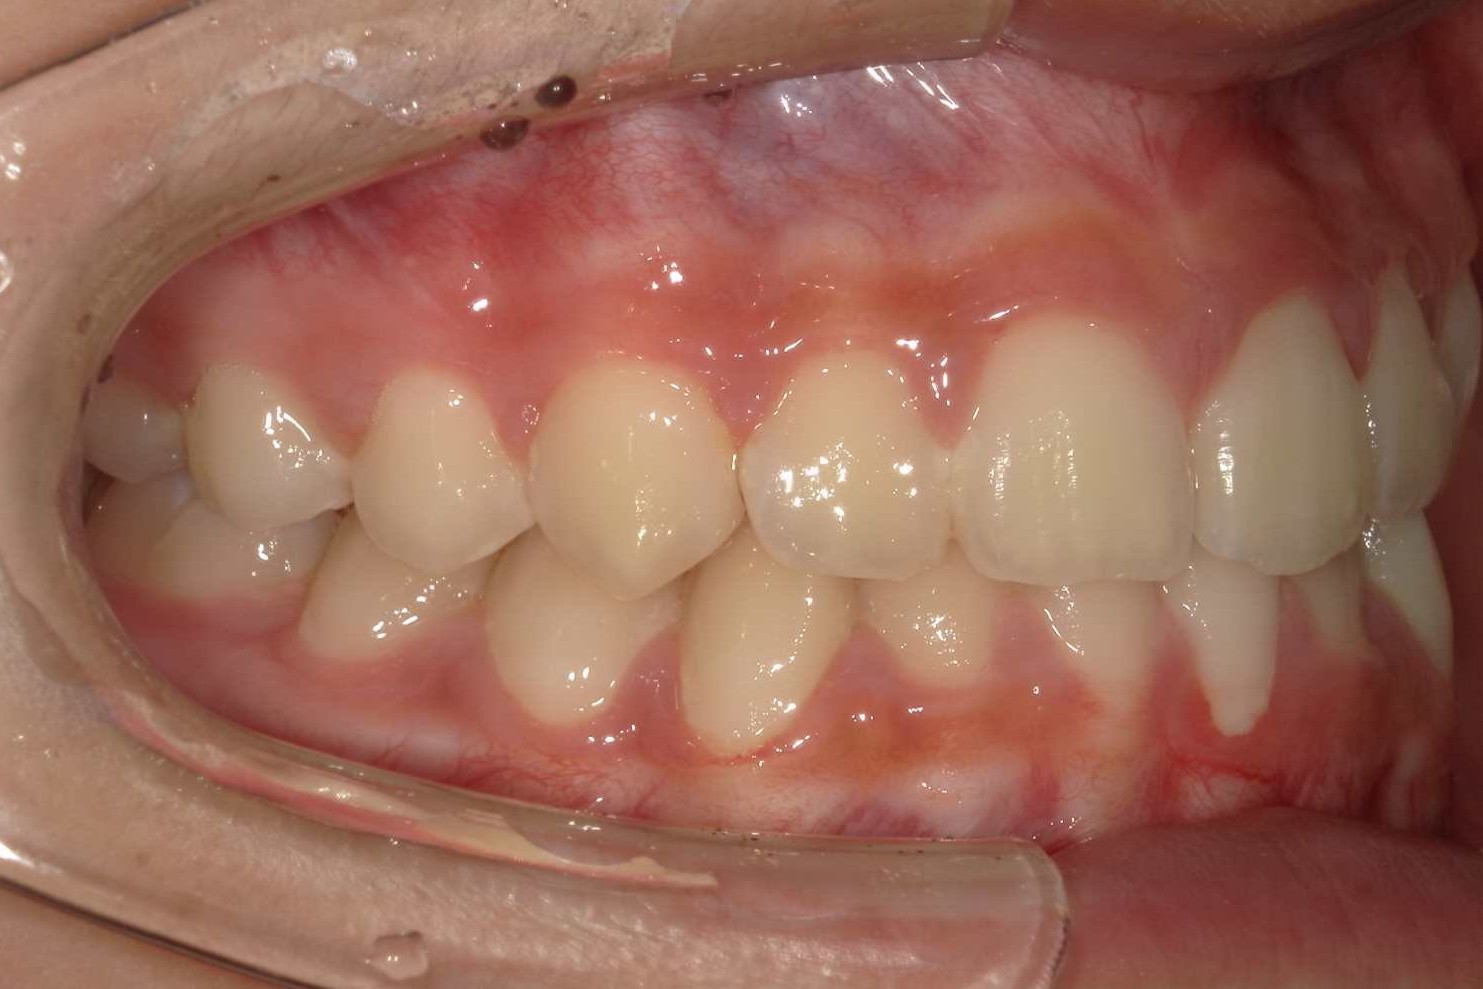

AFTER

| 年齢 | 8歳 |

|---|---|

| 主訴 | 出っ歯、かみ合わせの深さを治したい |

| 症状 | 過蓋咬合を伴う上顎前突症例 |

| 治療内容 | 過蓋咬合を伴う上顎前突症例と診断し床矯正装置、セクショナルアーチ、機能的矯正装置を用いて治療を行いました。 |

| 抜歯部位 | 非抜歯 |

| 治療期間 | 3年半 |

| 費用(税込) | 825,000円(税込)別途処置料 |

| 治療のリスク | 虫歯、歯周病の悪化、歯肉退縮、歯根吸収、顎関節症の悪化、後戻り |